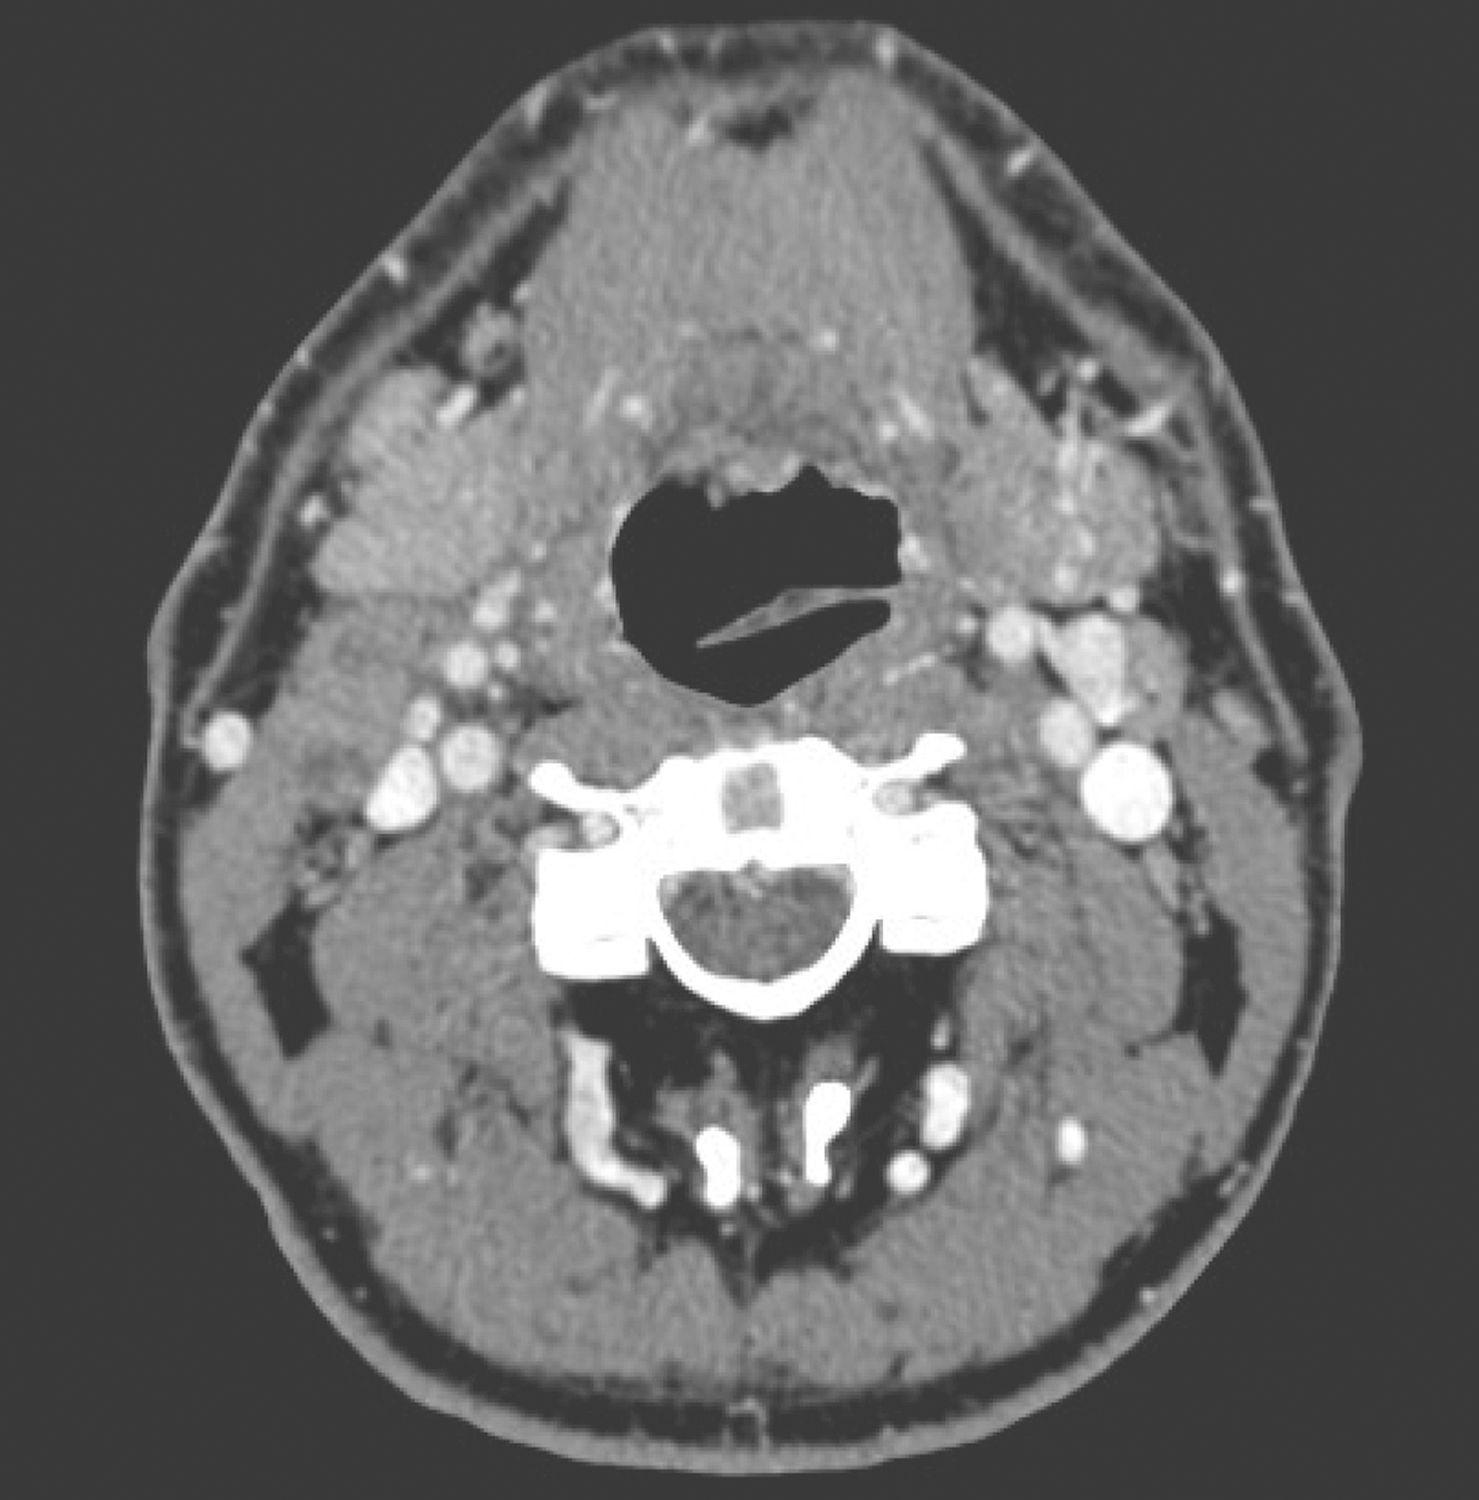

2.2014年1月10日颈胸部强化CT

右侧梨状窝内侧壁、右侧杓会厌皱襞局部软组织增厚,约4cm×3cm,形态不规则,累及右侧声门旁间隙和会厌前间隙,可见强化。右侧Ⅱ区胸锁乳突肌内侧可见数枚肿大淋巴结,约2cm×1.5cm大小,可见环形强化,边界不清(图4~图6),纵隔、双肺门未见肿大淋巴结。CT诊断:下咽恶性肿瘤并颈部淋巴结转移表现。

图4右侧Ⅱ区胸锁乳突肌内侧可见数枚肿大淋巴结